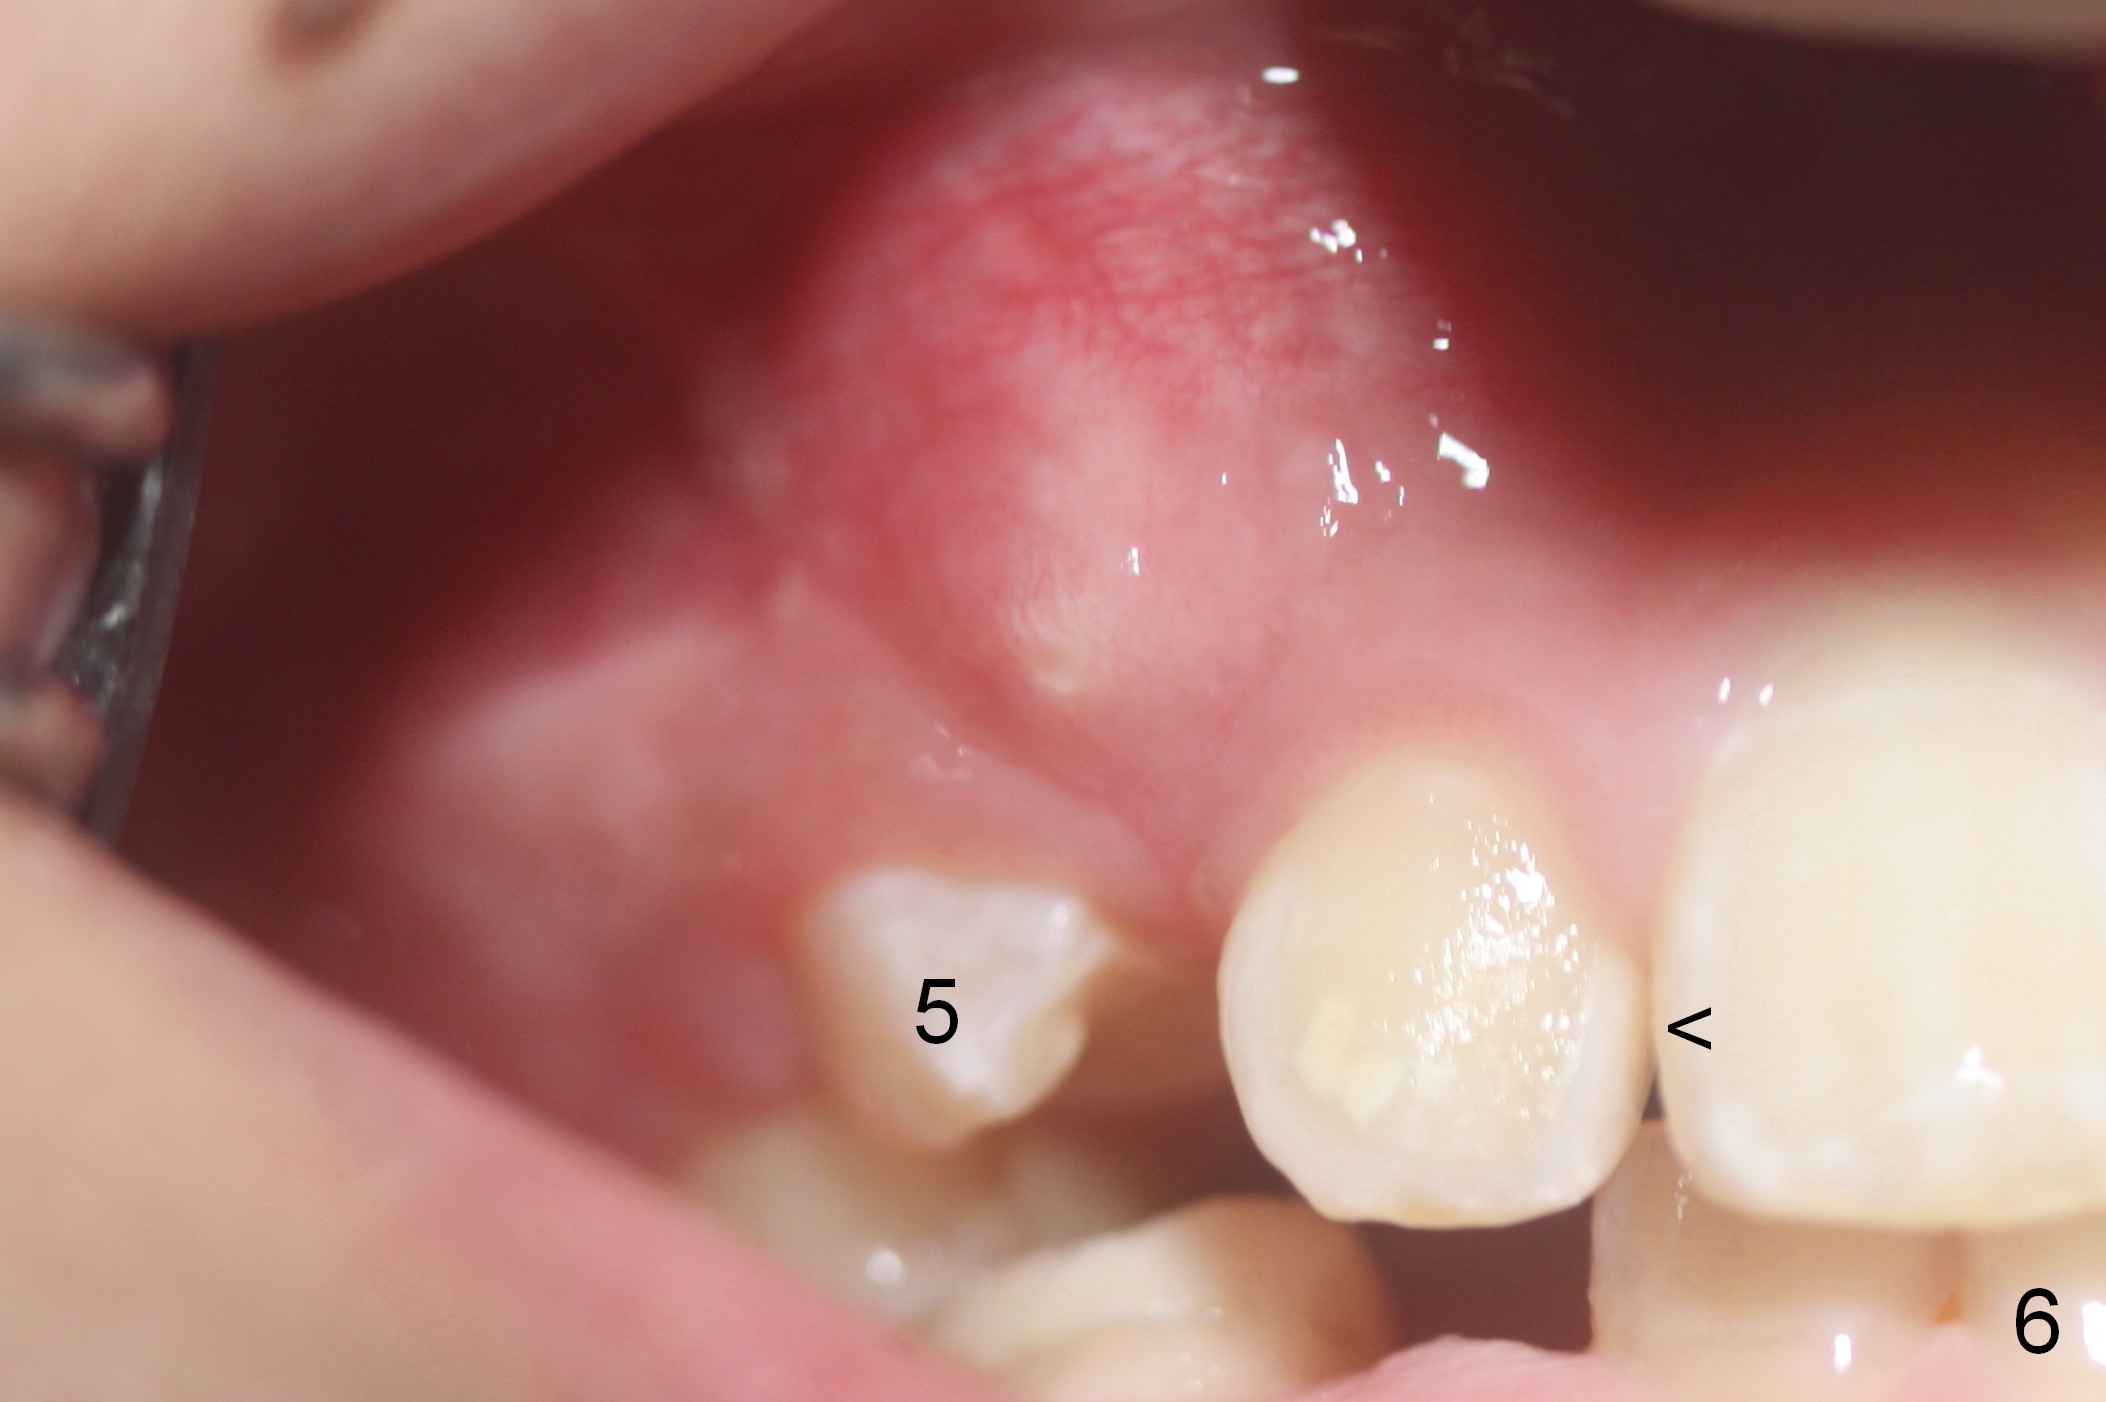

For upper and lower right crowding, series extraction is planned. First the tooth B is extracted. Within 1.5 months, the tooth #5 is erupting (Fig.4 (9 years 4 months old)). It will be extracted once it is fully erupted.

One month later, the tooth #5 erupts more (Fig.5,6) and is extracted (Fig.8-10). The tooth S is to be extracted to make room for #27 and 28 eruption (Fig.7).

Another 1 month, the teeth #4 and 6 are erupting (Fig.11,12). The tooth A is to be extracted. It is assumed that the diastema between #7 and 8 (due to #7 mesial shift in turn due to #6 erupting, Fig.11 arrow (as compared to Fig.6 <)) will be closed once the tooth #6 erupts fully.